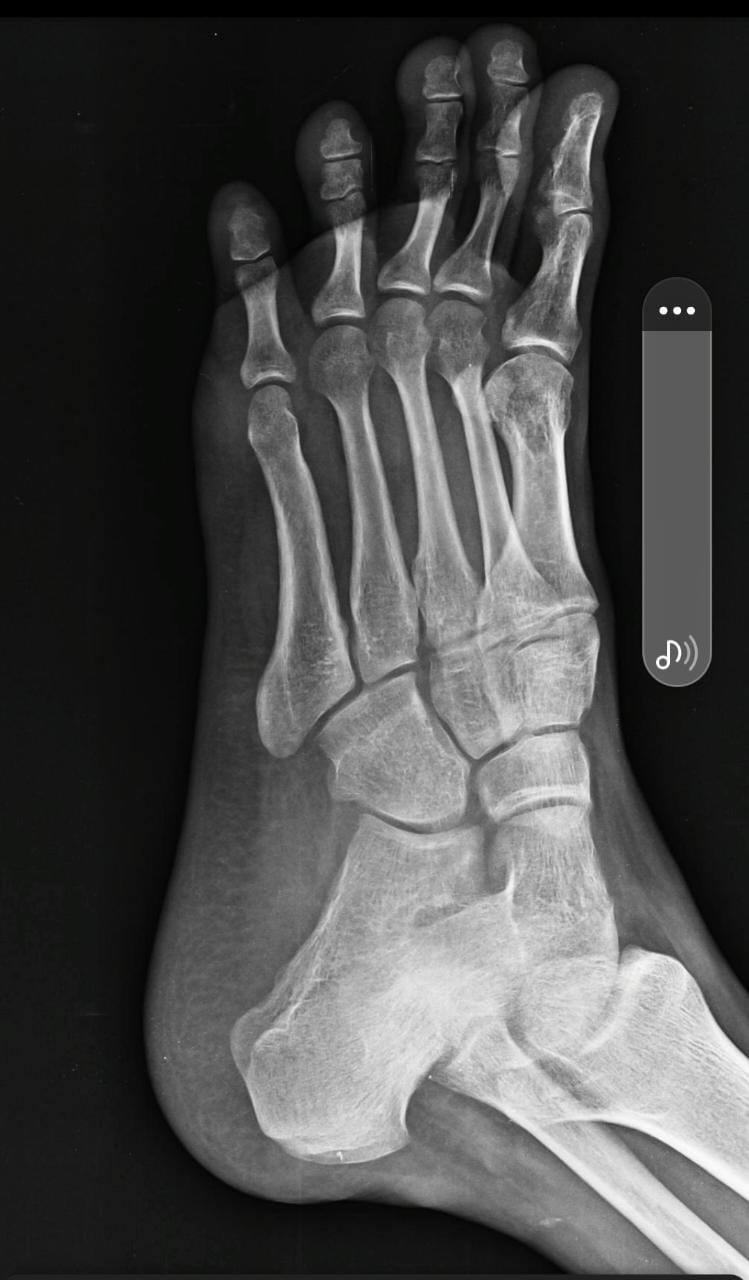

I need your help for my ankle sprain

I am suffering from ankle sprain problem from 20th November to till. I am still not able to walk properly. Please help me.